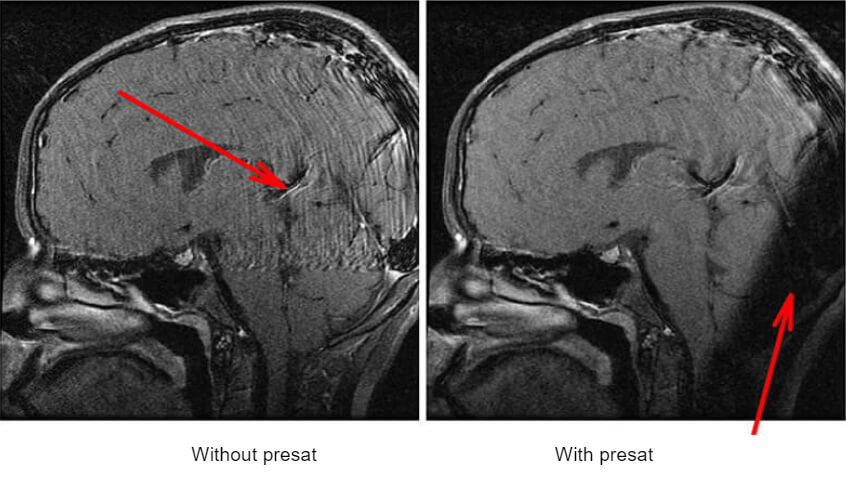

The RF wave applied covers all the rotation frequencies of the hydrogen protons of the section: all protons in the section are flipped 90° and the others are untouched. If we now apply the standard sequence. Protons inside the pre-saturation band will not have a transverse component and will thus not give a signal. These pre-saturation bands are called Sat on GE, Rest Slab on Philips or Reg. Saturation on Siemens. Example of using a saturation band to eliminate involuntary motion. The venous flow in the back of the brain is causing an artifact.

Here we have an example of using a saturation band to eliminate involuntary motion. The venous flow in the back of the brain is causing an artifact. On the second image, we see a dark band. This is a pre-saturation pulse band. It works along with the same principle of the gradients. The protons in this area will not present at the same rate as the rest of the protons in the image, thus they will not contribute signal or motion to the image.

Comparison of Fat Sat and Pre Sat

Fat sat and pre-saturation operate with similar mechanisms: they use a selective pulse just before the sequence. Fat sat sends a selective pulse to the entire volume but at a very precise frequency by adjusting the emission bandwidth. Pre-saturation sends a selective pulse overall frequencies but creates resonance at a precise location by the use of a section selection gradient.